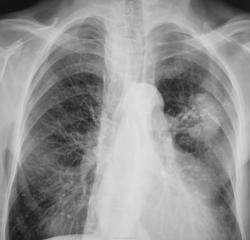

Контроль после флюорографии. "Архива" нет.

Bl.pulm.sin? рекомендована ФБС.

Образование скорее всего периферический рак. Контуры хоть и ровные, но присутствует дорожка к корню. Да и небольшой ателектаз всё-таки есть, участок просветления.

Предположу центральный C-r 3-го сегментарного бронха.

о силикотуберкулеме, т.к. тень высокой интенсивности,неоднородной структуры с вкраплениями кальцинатов. выявлена при проверочной флюорографии. При них может наблюдаться ателектазы. отсюда и вопрос опрофанамнезе

Думаю, переферический BL S-3 с вовлечением ВГЛУ и ателектазом в/д...

Может, сосудистая мальформация? Что-то больно корень спокоен, просто до противного... Или спать пора).

Согласен с раком в S3 слева.

Стойкое впечатление, что не рак это, а что-то очень старое. Только что - пока придумать не могу. Множественные обизвествленные лимфоузлы?

Рак это периферический в 3 сегменте, но достиг и среднедолевого  бронха, поэтому ателектаз средней доли. А нижняя доля компенсаторно "вздута". Ну, это, может, только я так думаю, а на самом деле узнаем позже.

В левом легком нет средней доли.Это-ателектаз язычковых сегментов.А в остальном я с Вами согласен.

послетуберкулезные изменения